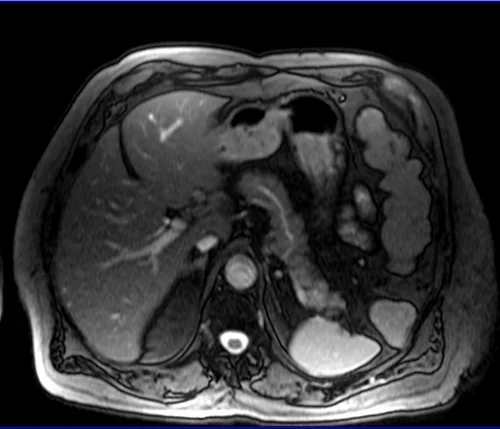

ABDOMEN AXIAL